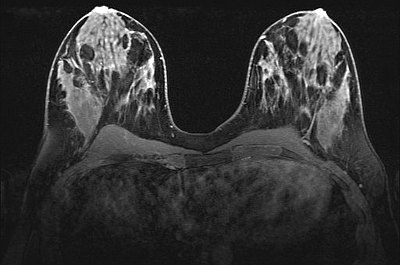

Das Institut für diagnostische Radiologie führt die MR-Diagnostik auf Anforderung der Sprechstunde des Zentrums durch.